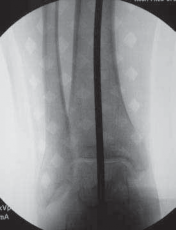

2. Before the osteotomy is performed, an intraoperative mechanical axis view should be obtained, using either

the Bovie cord or the alignment rod found in the osteotomy set.

4. Using fluoroscopy, the alignment rod is placed at the center of the femoral head (

TECH FIG 3A

) and then at the center of the ankle joint (

TECH FIG 3B

).

D E TECH FIG 3•A.

Fluoroscopic image of alignment rod through femoral head.

B.

Fluoroscopic image of the alignment rod in the center of the ankle.

C.

The subsequent location of the alignment rod in the knee. This initial mechanical axis must be corrected. It should match with the preoperative planning.

1. The subsequent location of the alignment rod in the coronal view of the knee is the intraoperative location of the mechanical axis (

TECH FIG 3C

2. These radiographs are saved for later comparison.